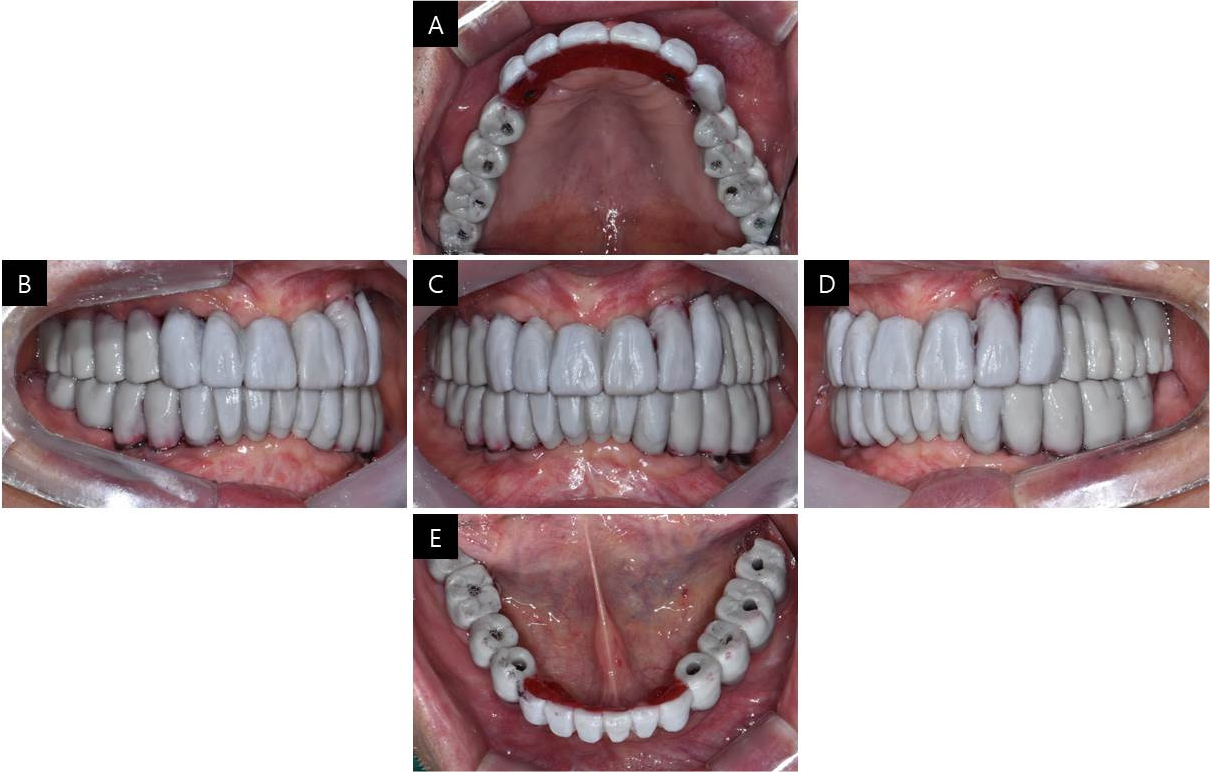

After two months of the second-stage surgery, impressions were taken using individual trays and pick-up type impression copings (US Fixture Pick-up Impression Coping; Osstem Implant, Busan, Korea), with silicone impression material (Imprint II; 3M ESPE, St. Paul, MN, USA) for provisional restoration. For more accurate restoration, the impression copings were splinted with autopolymerizing acrylic resin (Pattern Resin; GC Corporation, Tokyo, Japan) on the master cast from the first impression procedure at least 24 hours before being sectioned to compensate for shrinkage.15,16 Then, they were reconnected in the mouth with Pattern Resin for the second impression procedure (Fig. 2).

To decide which abutment to select, master casts were fabricated, and implant angulation was found to be parallel enough to restore it in a one-piece superstructure. Since the patient was well adapted to the vertical dimension of the former dentures, it was once again applied on provisional fixed implant prosthesis, and centric relation was guided using lucia jig to be transferred on a semi-adjustable articulator. Provisional restorations were designed through CAD software and delivered in the mouth with temporary cylinders. To verify the vertical dimension of the provisional restoration, a TMJ series was taken, and both condyles were within normal limits.